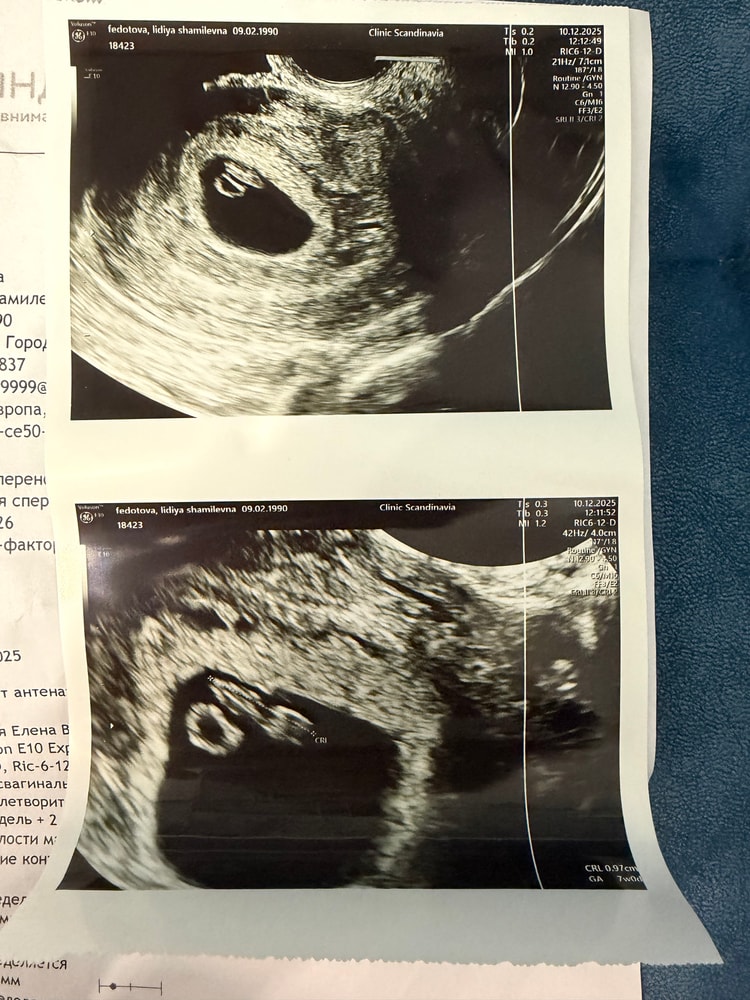

Обследования, узи, анализыДевочки привет) я писала 05.12 делала первое узи в жк. Информации очень мало и сделано было секунд за 40 максимум. Сказала что отстает от акушерского срока. Я прикреплю это узи(первое фото первого узи). Сегодня 10.12 сходила в Скандинавию, всё хорошо, на огромном мониторе посмотрела на свою ляличку 🥹, всё расписали, всё показали, как же круто🩷🩷🩷 даже видно было как стучит сердечко 🫶🏻. Девчат, я так счастлива, даже не могу в себя прийти 🥹🥹🥹🥹🥹🥹🥹🥹 И кстати всё соответствует сроку😌

Видеть сердечко малыша - это огромное счастье и облегчение. Желаю, чтобы вся беременность протекала так же легко и радостно.🌟